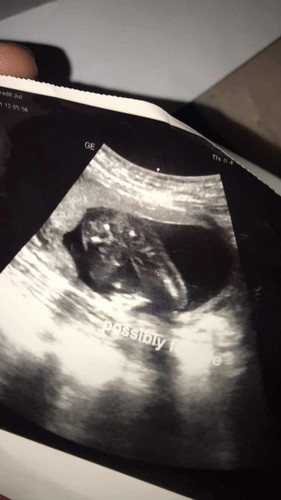

19+2แม่ๆคิดว่าเป็นผญหรือผชค่ะหมอไม่มั่นใจให้มาเป็นผญ80%

น่าจะ ญ นะคะ